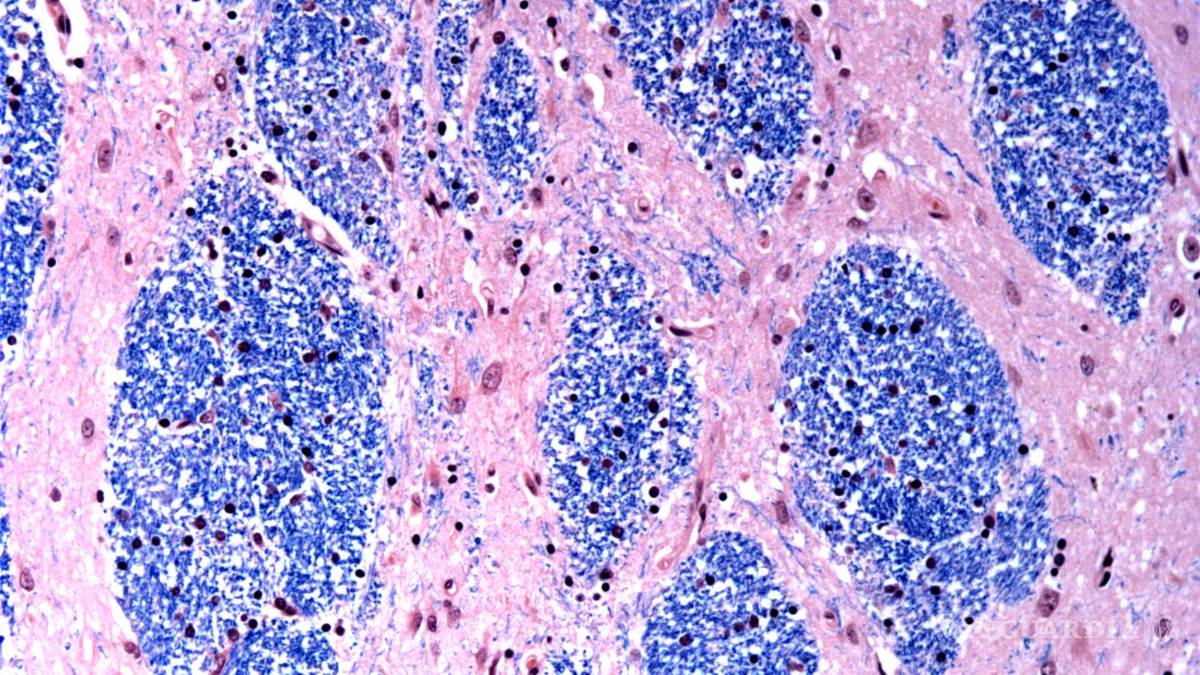

Científicos del Broad Institute de MIT y Harvard, el Hospital McLean en Massachusetts y la Facultad de Medicina de Harvard estudiaron tejido cerebral donado por 53 personas con Huntington y 50 sin ella, analizando medio millón de células.

$!Los científicos están desentrañando el misterio de qué es lo que desencadena la enfermedad de Huntington, un trastorno hereditario devastador y mortal.

Se centraron en la mutación de Huntington, que involucra un tramo de ADN en un gen particular donde una secuencia de tres letras, CAG, se repite al menos 40 veces. En personas sin la enfermedad, esta secuencia se repite sólo de 15 a 35 veces. Descubrieron que los tramos de ADN con 40 o más “repeticiones” se expanden con el tiempo hasta que tienen cientos de CAGs. Una vez que los CAGs alcanzan un umbral de aproximadamente 150, ciertos tipos de neuronas enferman y mueren.